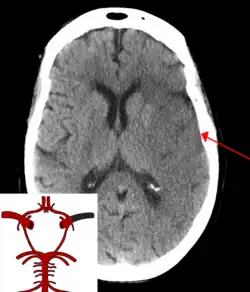

CT scan of an intraparenchymal bleed (bottom arrow) with surrounding edema (top arrow)

A CT showing early signs of a middle cerebral artery stroke with loss of definition of the gyri and grey white boundary

Dense artery sign in a patient with middle cerebral artery infarction shown on the left. Right image after 7 hours.